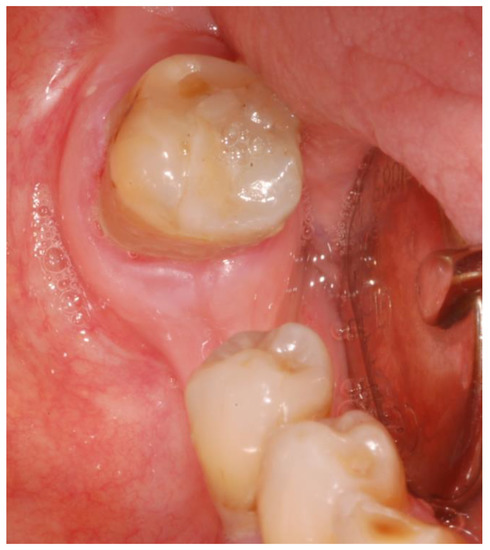

- Surgery timing. The surgeon can follow in real time the ultrasonic tip position onto the system screen displaying the CBCT images and safely identify and remove the necrotic bone surrounding the inferior alveolar nerve on the right side.